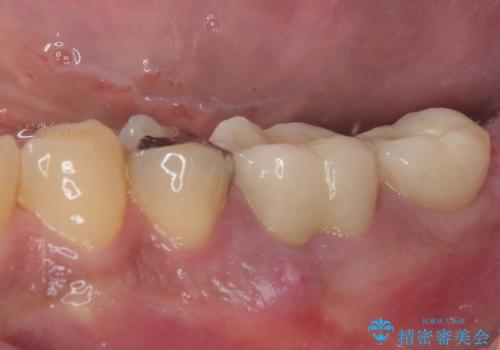

- むし歯による奥歯の痛みを気にして来院された患者様です。

神経にまでむし歯の及んでいる歯や、既に根管治療がされている歯に痛みがあったため、まずは根管治療を行うこととしました。

その後、以前行った抜歯矯正の後戻りをインビザライン・ライトにより改善し、むし歯や銀歯はオールセラミッククラウンにて補綴治療することとしました。